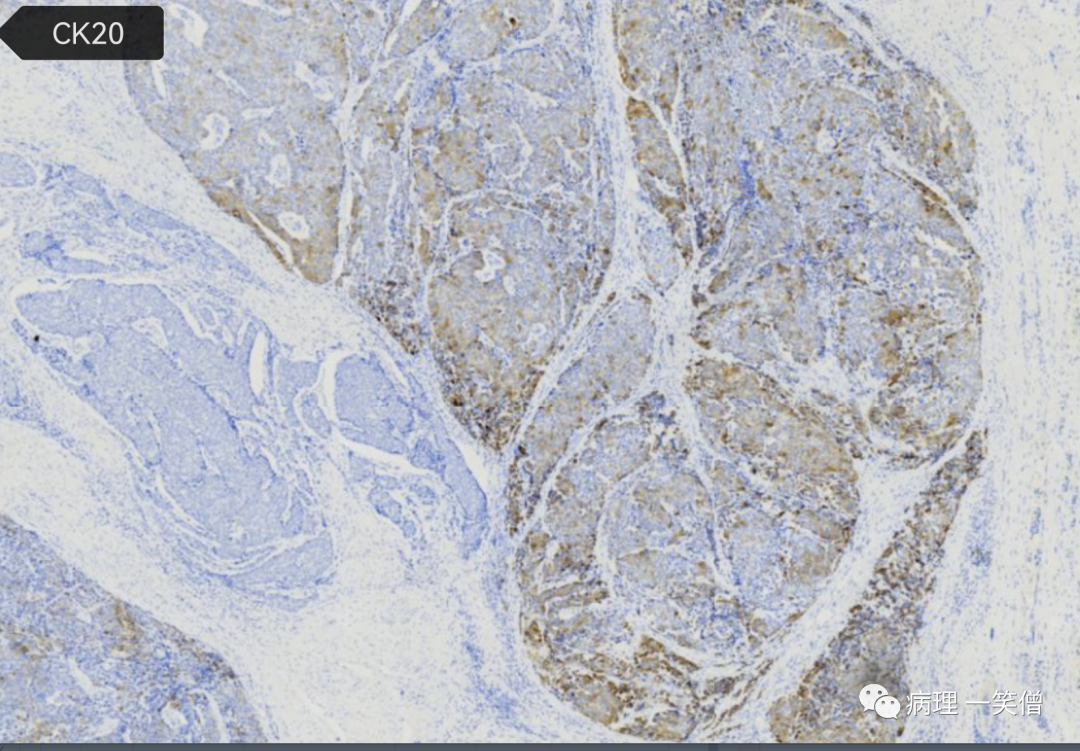

特殊染色及免疫组化:

均见胞质内 D‑PAS 呈阳性表达的肿瘤细胞。

均呈现 2 种以上的神经内分泌标志物阳性。

对呈突触素阳性患者 进行突触素/D‑PAS 双染,结果显示肿瘤内均可见 同时具有 2 种成分阳性表达的单个肿瘤细胞。

在诊断AC时最好同时行3种神经内分泌标志物的免疫组织化学检测和D‑PAS的特殊染色检测,可以显示肿瘤细胞的双向分化特征,排除单纯低分化腺癌或神经内分泌癌。